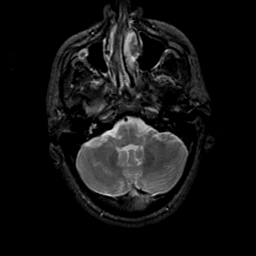

MR Study #23, January 26, 1992 -- Slice #10